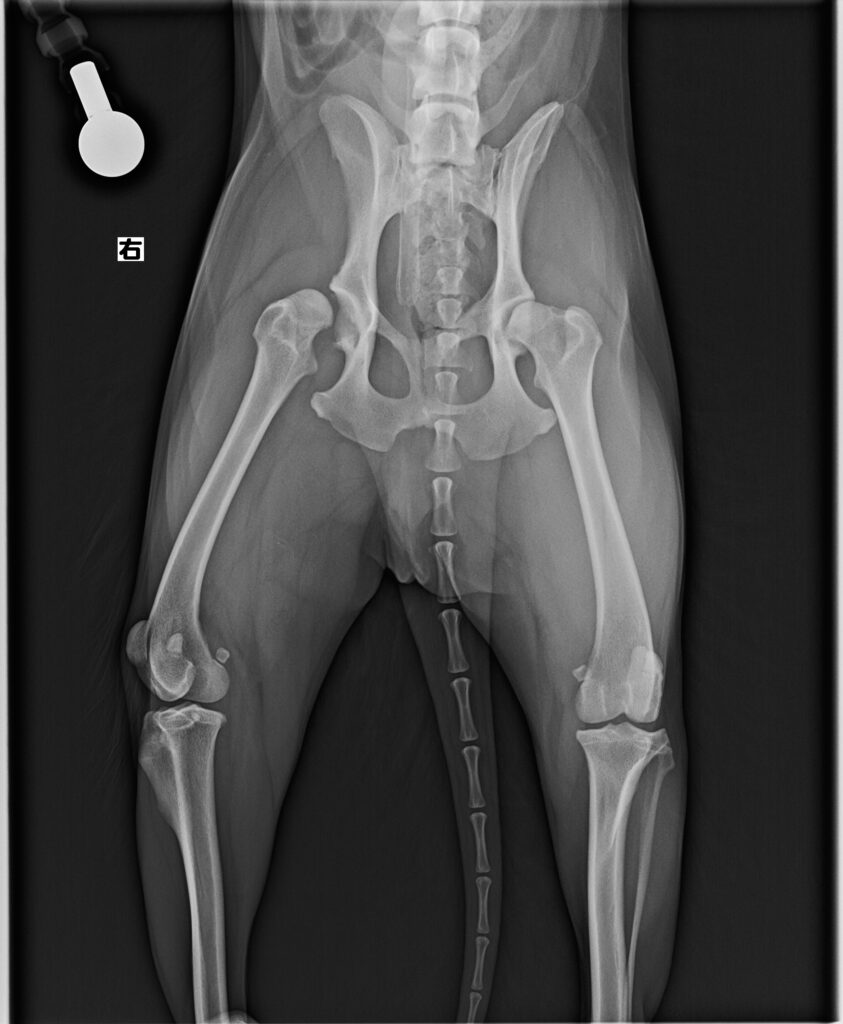

- 診断名:両側性変形性股関節骨関節症(股関節形成不全に由来すると考えられる)を伴う右側股関節脱臼

整形外科的検査では、股関節の可動域、疼痛誘発、関節の不安定性を評価し、対側にも開排・伸展で違和感が示唆されました。血液・凝固検査は、全身麻酔と骨盤・大腿骨手術に耐えうる臓器機能や貧血、出血リスクの把握を目的に実施しました。レントゲン検査で、両側の股関節形成不全と変形性変化、患側の脱臼と骨頭・寛骨臼の形態変化を確認し、保存療法のみでのQOL維持が難しいと判断して股関節全置換術(THR)と大腿骨頭切除術(FHO)を治療選択肢として提示しました。